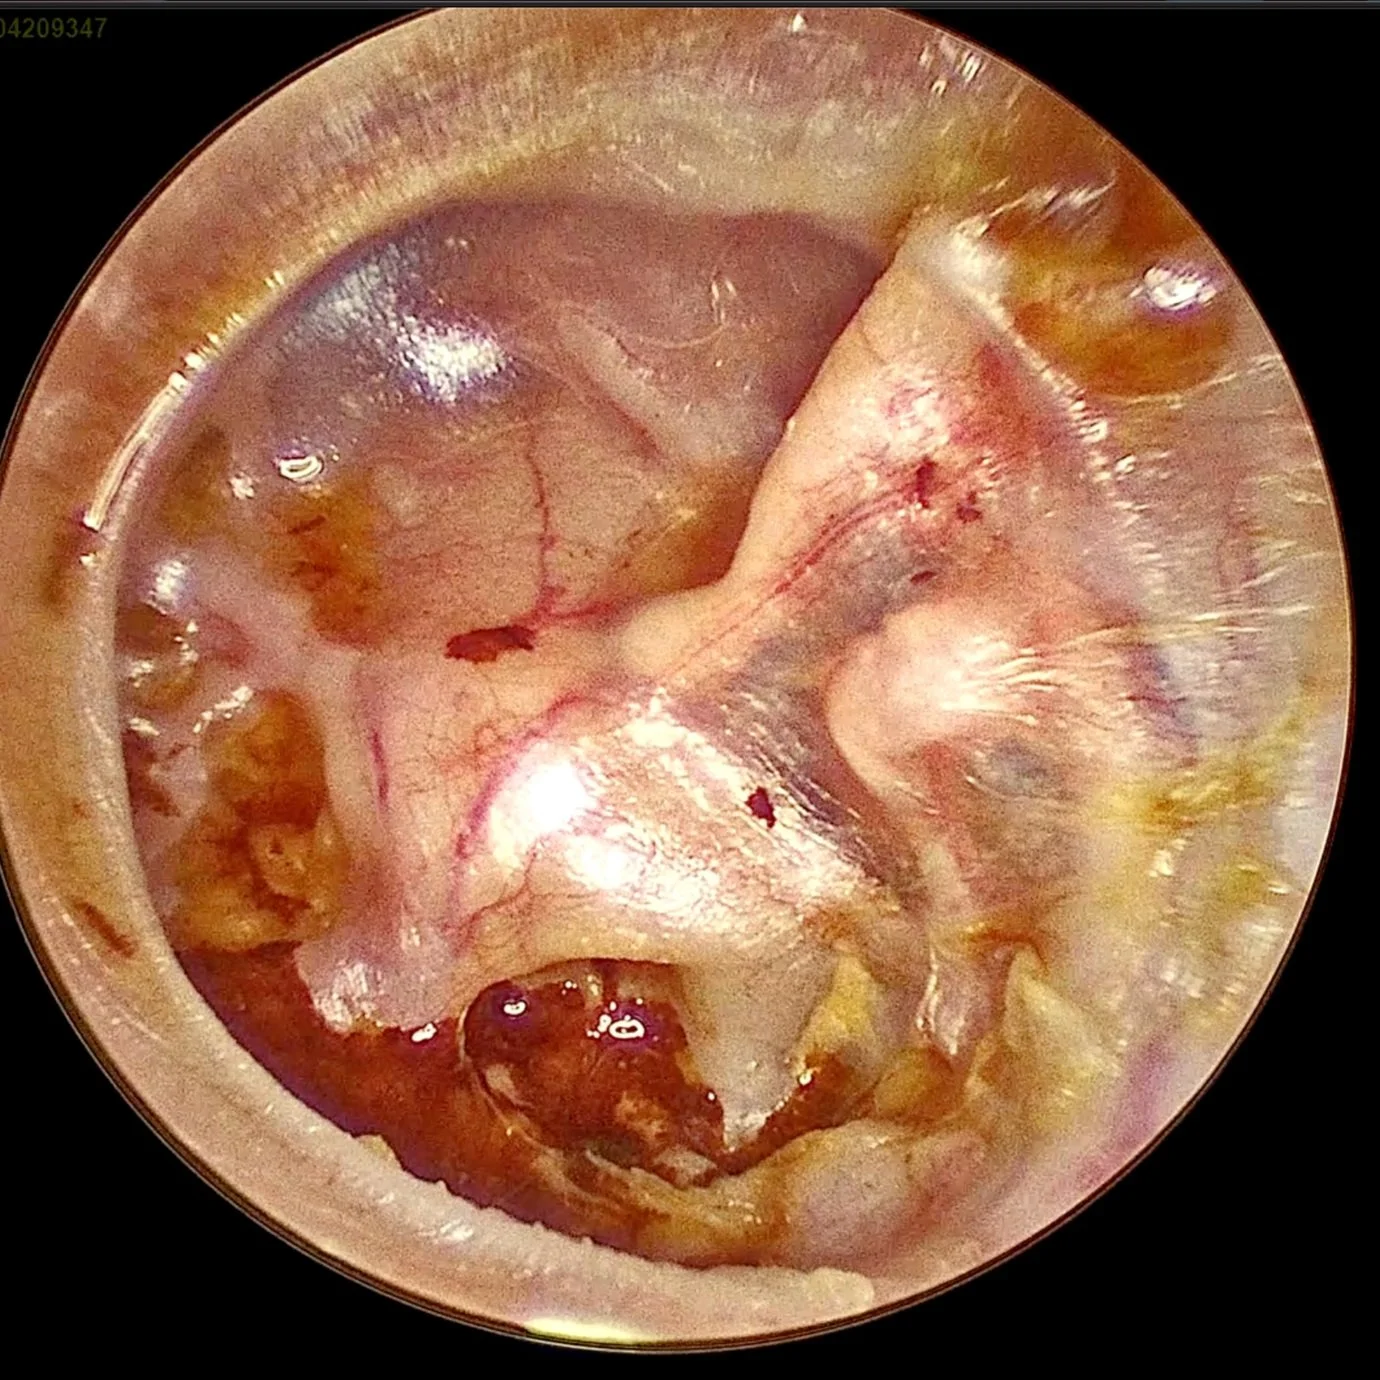

Endoscopic ear surgery (EES) is a minimally invasive method of performing procedures on the ear drum and surrounding structures. An endoscopic transcanal tympanoplasty is a surgical procedure that is used to repair a hole or tear in the eardrum (tympanic membrane). Different from the traditional technique which involves a cut behind the ear, the endoscopic technique is performed through the ear canal (transcanal) using an endoscope to visualize the inside of the ear. This allows for a smaller incision and less tissue dissection than traditional open tympanoplasty procedures.

During the procedure, the surgeon will make a small incision in the ear canal and use a small camera (an endoscope) to visualize the eardrum. The hole or tear in the eardrum is then closed using a patch of tissue, often taken from the patient's own ear canal (tragus cartilage). The patch is then secured in place using tiny surgical sponges.